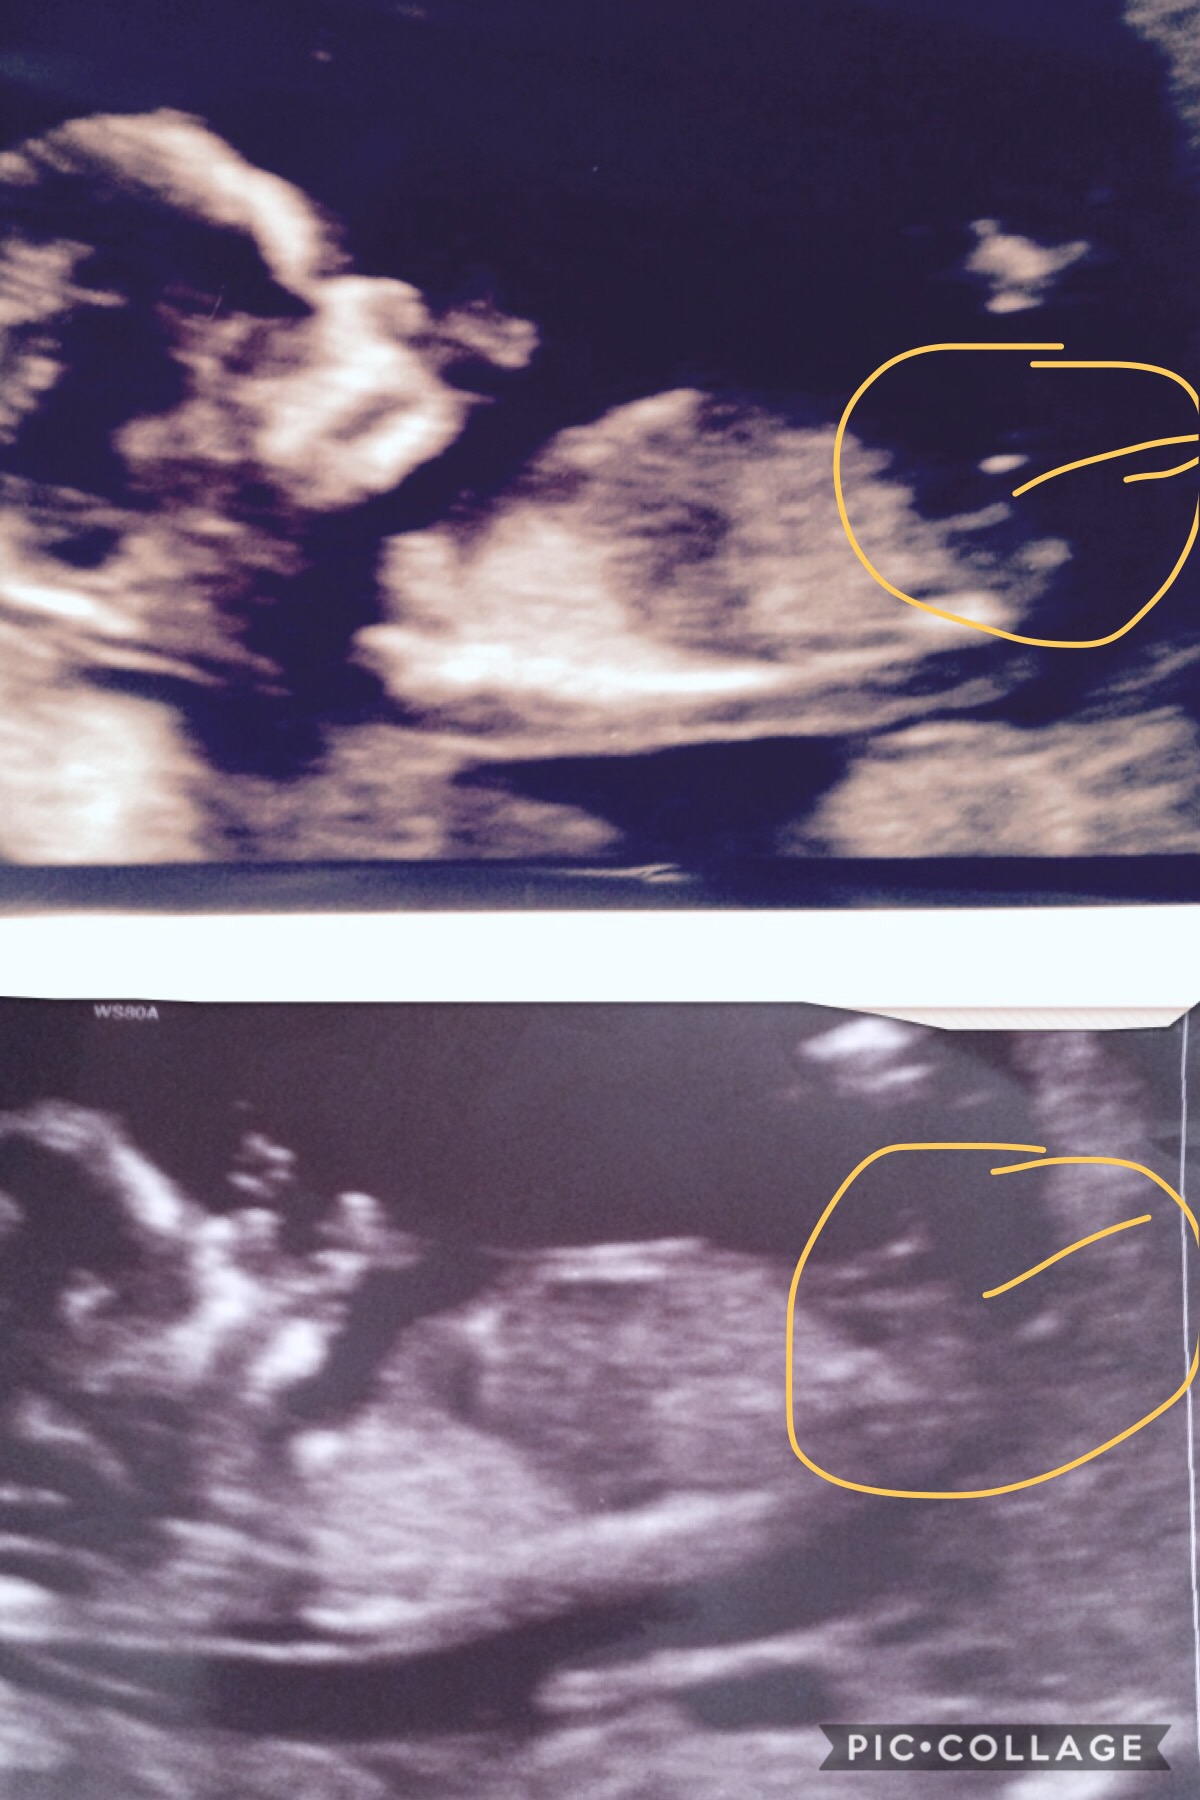

i am 13 weeks and 1 day on these pics is this the nub in the middle i was thinking girl but not really sure if it is one??Attachment 37375

I'm giving a slight girl lean. The nub does look girlie- I just can't tell if I see any stacking. My guess is a 55/45 girl lean

Think what's above is leg well looked like it in scan when she was showing us. Just seems more straight rather than pointing up thanks for the reply x

This one is tricky. Looks girly, but has a little rise to it. I will lean ever so slightly girl.

Is that the nub where I have circled as in another site they seem to think it's above but I'm pretty sure that's where baby's foot was in scan either way happy